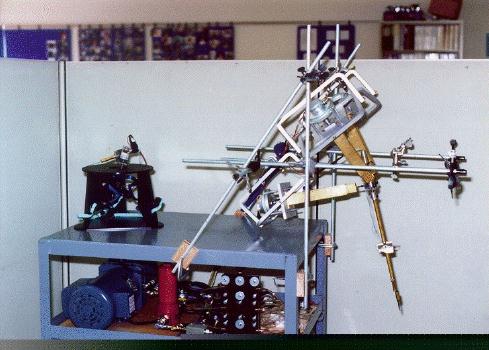

The robots used for automated surgery tend, at the present time, to be adapted industrial robots; for example, the PUMA robot arm. The reasons behind this are predominantly financial ones. Investing in the research and development of a robot for a specific task is highly expensive - costs running into millions of pounds, with no guarantee that a suitable product will be the outcome. Another hurdle is the lack of official safety guidelines and standards. Having brought up the fact that the surgeon is reliant upon the engineering behind the tools that they are using, it is clear that companies would not wish to risk possible legal proceedings should one of their products fail. (These issues will be further discussed in the section on safety). As it stands, industrial robots are adequate for the tasks involved, although it is hoped (and expected) that, in the future, surgery- specific robots will be developed and will become an industry of their own. Once the robotic procedure is initiated, sensors collect real-time data from the operating site and pass this to a display, via which the surgeon observes the operation. The type of sensor that seems to best suit the surgical application is the use of infra-red transmitters on the robot's 'joints', that are detected by cameras in the operating theatre (currently under commercial development by General Electric). From these, the exact position of the robot's appendages can be gauged and relayed back to the surgeon's display. It is an issue as to what control a surgeon should have when overseeing an automated surgery - as they may do more damage than good if they intervene. The most common arrangement is to have a 'stop' switch and perhaps a 'redo' control. Sensing the patient, intra-surgically, is fairly simple when using fiducials (the fiducials are specially made from materials that are easily detectable under the system being used). This is not the case, however, when using the preferred surface techniques. Here a variety of systems are under consideration, including an ultrasound sensor or an x-ray sensor - both mounted on a 'C-arm' so that they can move around the whole area of the patient. |